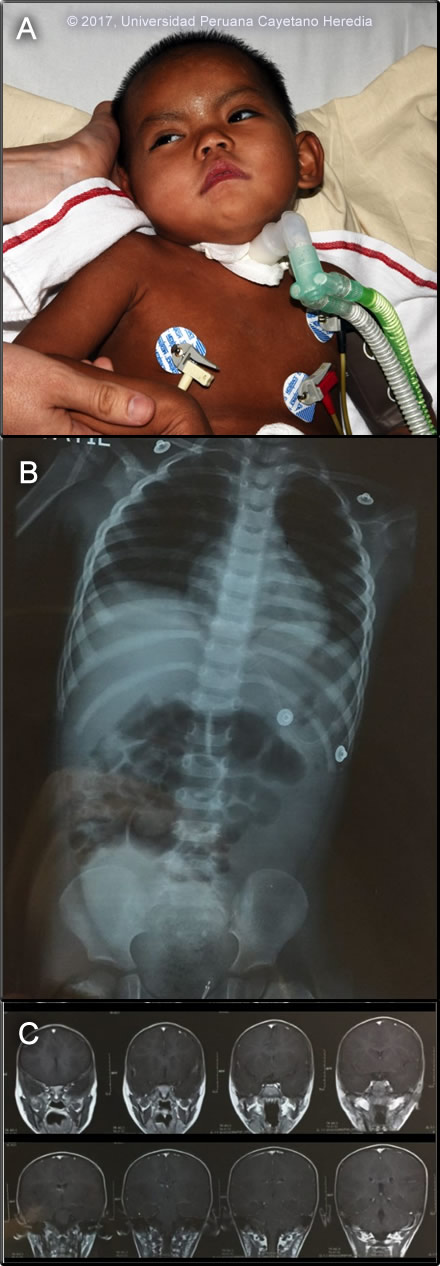

Epidemiology: Born and raised in an agricultural family in the Mayapo community, province of La Convencion in the jungle of Cuzco department. She had no history of malaria, was unvaccinated for yellow fever, and had no known exposure to TB. She had received 1 ml. doses of tissue culture rabies vaccine 11 and 4 days prior to the onset of fever as part of a pre-exposure vaccination campaign in her community following some earlier encephalitic fatalities. Physical Examination (arrival at our ER): HR 108, RR 32, BP 89/33 mmHg, T 37ºC, SatO2 95% Acutely ill patient. Skin: no rash. Chest: diffuse rhonchi bilaterally. CV: regular, tachycardic, multifocal murmur II/VI. Abdomen: bowel sounds present, no tenderness, no pain. Neurologic: Glasgow 12/15, somnolent, not following verbal commands. Opens her eyes after painful stimuli and localizes pain. Hypotonic, muscle strength not assessed. Normal reflexes, Babinski negative, no clonus, Hoffman negative. No meningeal signs. Image A shows the child in the ICU. Laboratory Examination: WBC 19.9 (2 bands, 73 segmented neutrophils, 3 eos, 7 monos, 15 lymphs), Hb 7.6 g/L, platelet count 494 000 /uL. Glucose 85 mg/dL, BUN 9 mg/dL, creatinine 0.3 mg/dL. Total protein 6.6 g/dL, albumin 3.2 g/dL. Total bilirubin 0.4 mg/dL AST 36 U/L, ALT 25 U/L, AP 166 U/L. CXR and MRI are shown in Image B and Image C. CSF: WBC 79 cells/hpf (90% lymphocytes), RBC 25 cells/hpf, glucose 51 mg/dL, protein 91 mg/dL. Malaria smear negative.